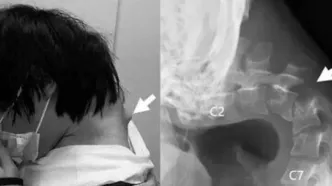

بیماری سندرم سر افتاده چه علائمی دارد؟/ عکس